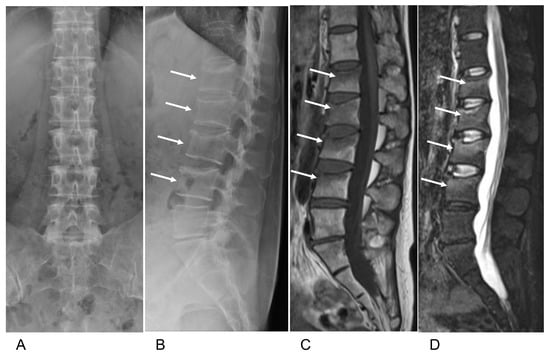

2. Case Presentation